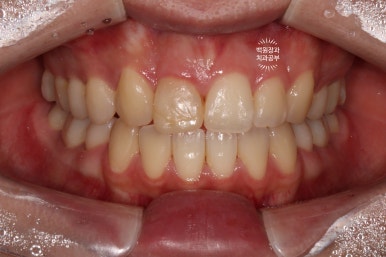

Before & After

치아미백과 잇몸성형술 그리고 단 한개의 지르코니아 크라운을 통해 얻은 심미적인 결과입니다!

치아는 보다 밝아졌고, 앞니는 더 나란히 - 가지런해진 모습이 훨씬 보기 좋아졌네요 :)